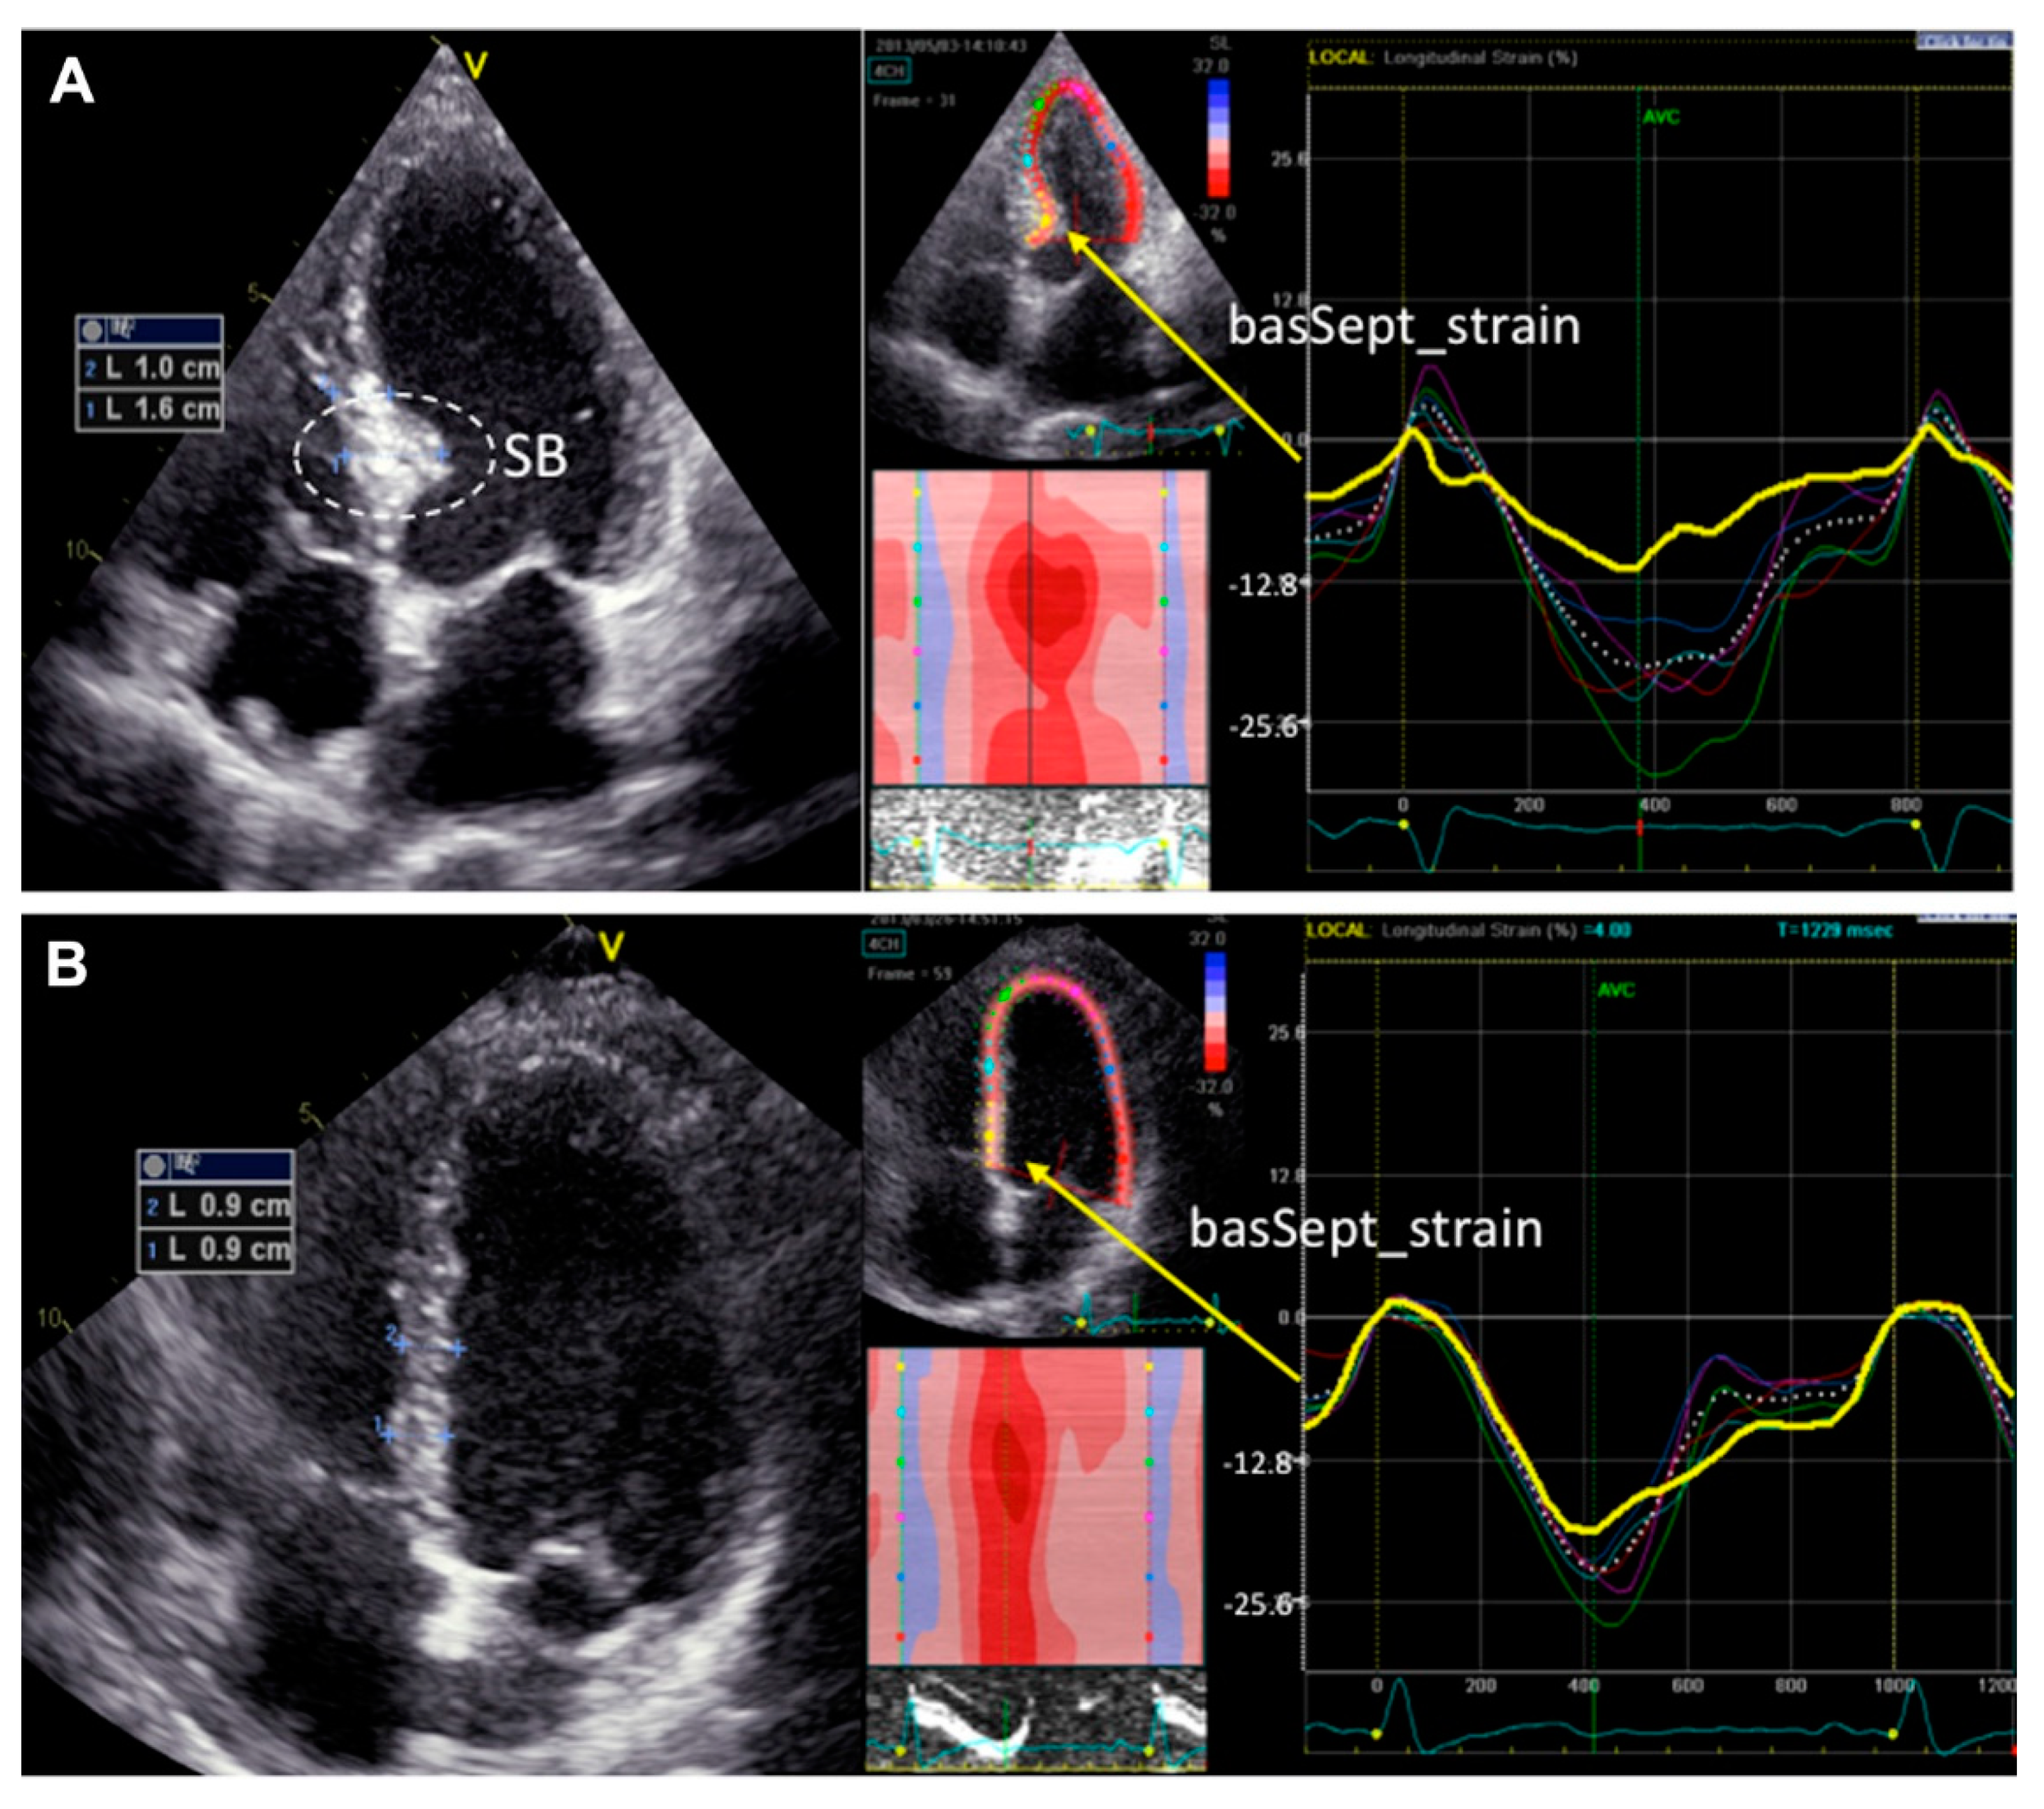

4.2. Basal Septal Hypertrophy (Upper Septal Hypertrophy or ‘Sigmoid Septum’)

- Loncaric, F.; Nunno, L.; Mimbrero, M.; Marciniak, M.; Fernandes, J.F.; Tirapu, L.; Fabijanovic, D.; Sanchis, L.; Doltra, A.; Cikes, M.; et al. Basal Ventricular Septal Hypertrophy in Systemic Hypertension. Am. J. Cardiol. 2020, 125, 1339–1346. [Google Scholar] [CrossRef] [PubMed] [Green Version]

- Gaudron, P.D.; Liu, D.; Scholz, F.; Hu, K.; Florescu, C.; Herrmann, S.; Bijnens, B.; Ertl, G.; Stork, S.; Weidemann, F. The septal bulge—An early echocardiographic sign in hypertensive heart disease. J. Am. Soc. Hypertens. 2016, 10, 70–80. [Google Scholar] [CrossRef] [PubMed] [Green Version]

- Saeed, S.; Edvardsen, T. Basal septal hypertrophy in hypertension; about time to introduce an objective and reproducible quantification. J. Hypertens. 2021, 39, 1316–1318. [Google Scholar] [CrossRef]

- Yalcin, F.; Yalcin, H.; Kucukler, N.; Arslan, S.; Akkus, O.; Kurtul, A.; Abraham, M.R. Basal Septal Hypertrophy as the Early Imaging Biomarker for Adaptive Phase of Remodeling Prior to Heart Failure. J. Clin. Med. 2021, 11, 75. [Google Scholar] [CrossRef]